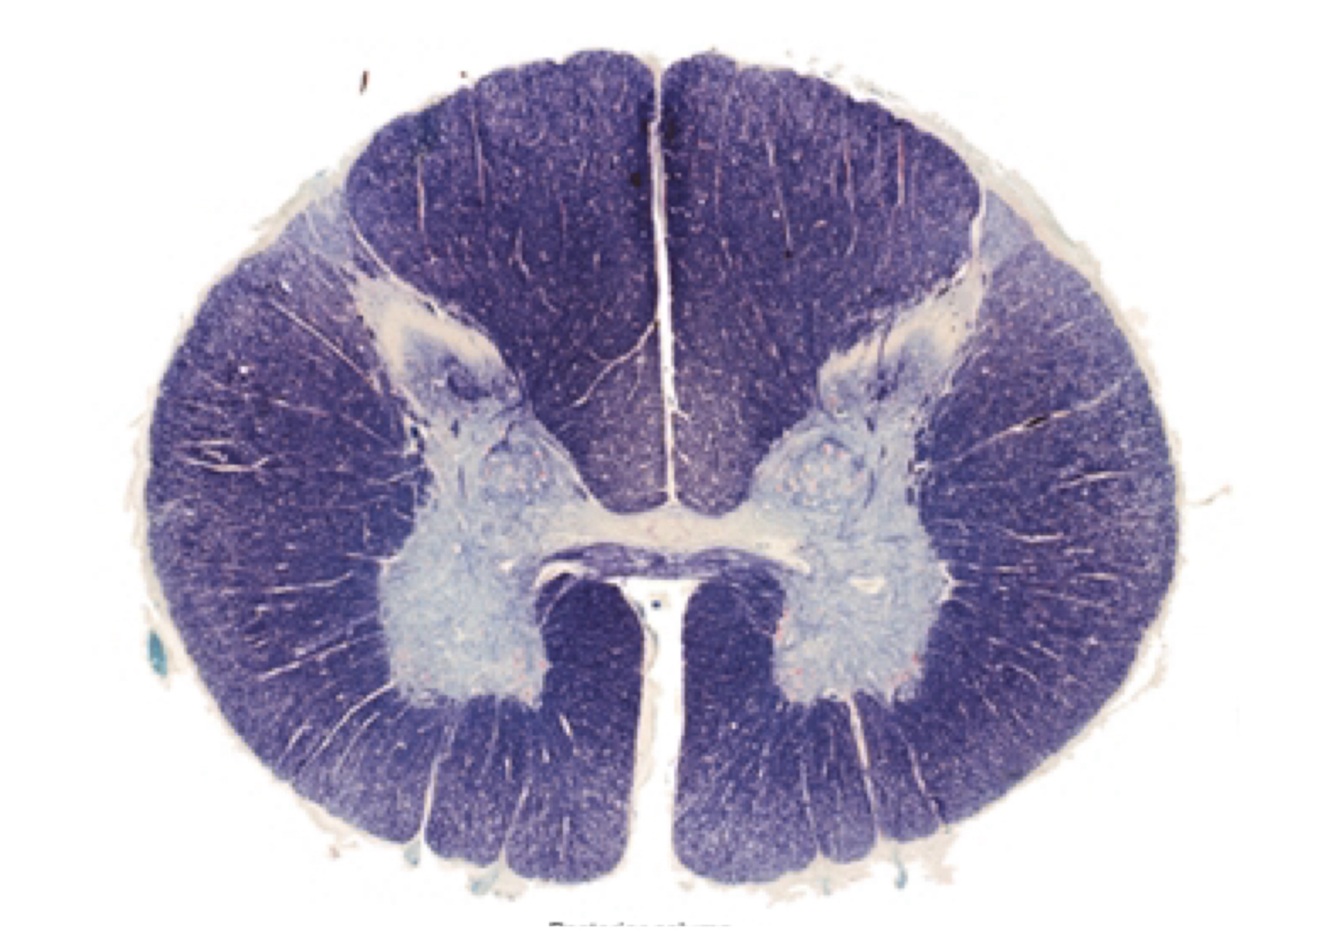

Parts of the spinal cord

Cervical, thoracic/dorsal, lumbar, sacral (conus medullaris-roots that go down).

What is grey matter?

Mostly cells bodies, also glia and vessels

What is white matter?

Mainly axons (in nerve fibers) and oligodendrocytes (mielin), also glia and vessels

Gray matter in the spinal cord is … while white matter is…

In the middle, in the outside.